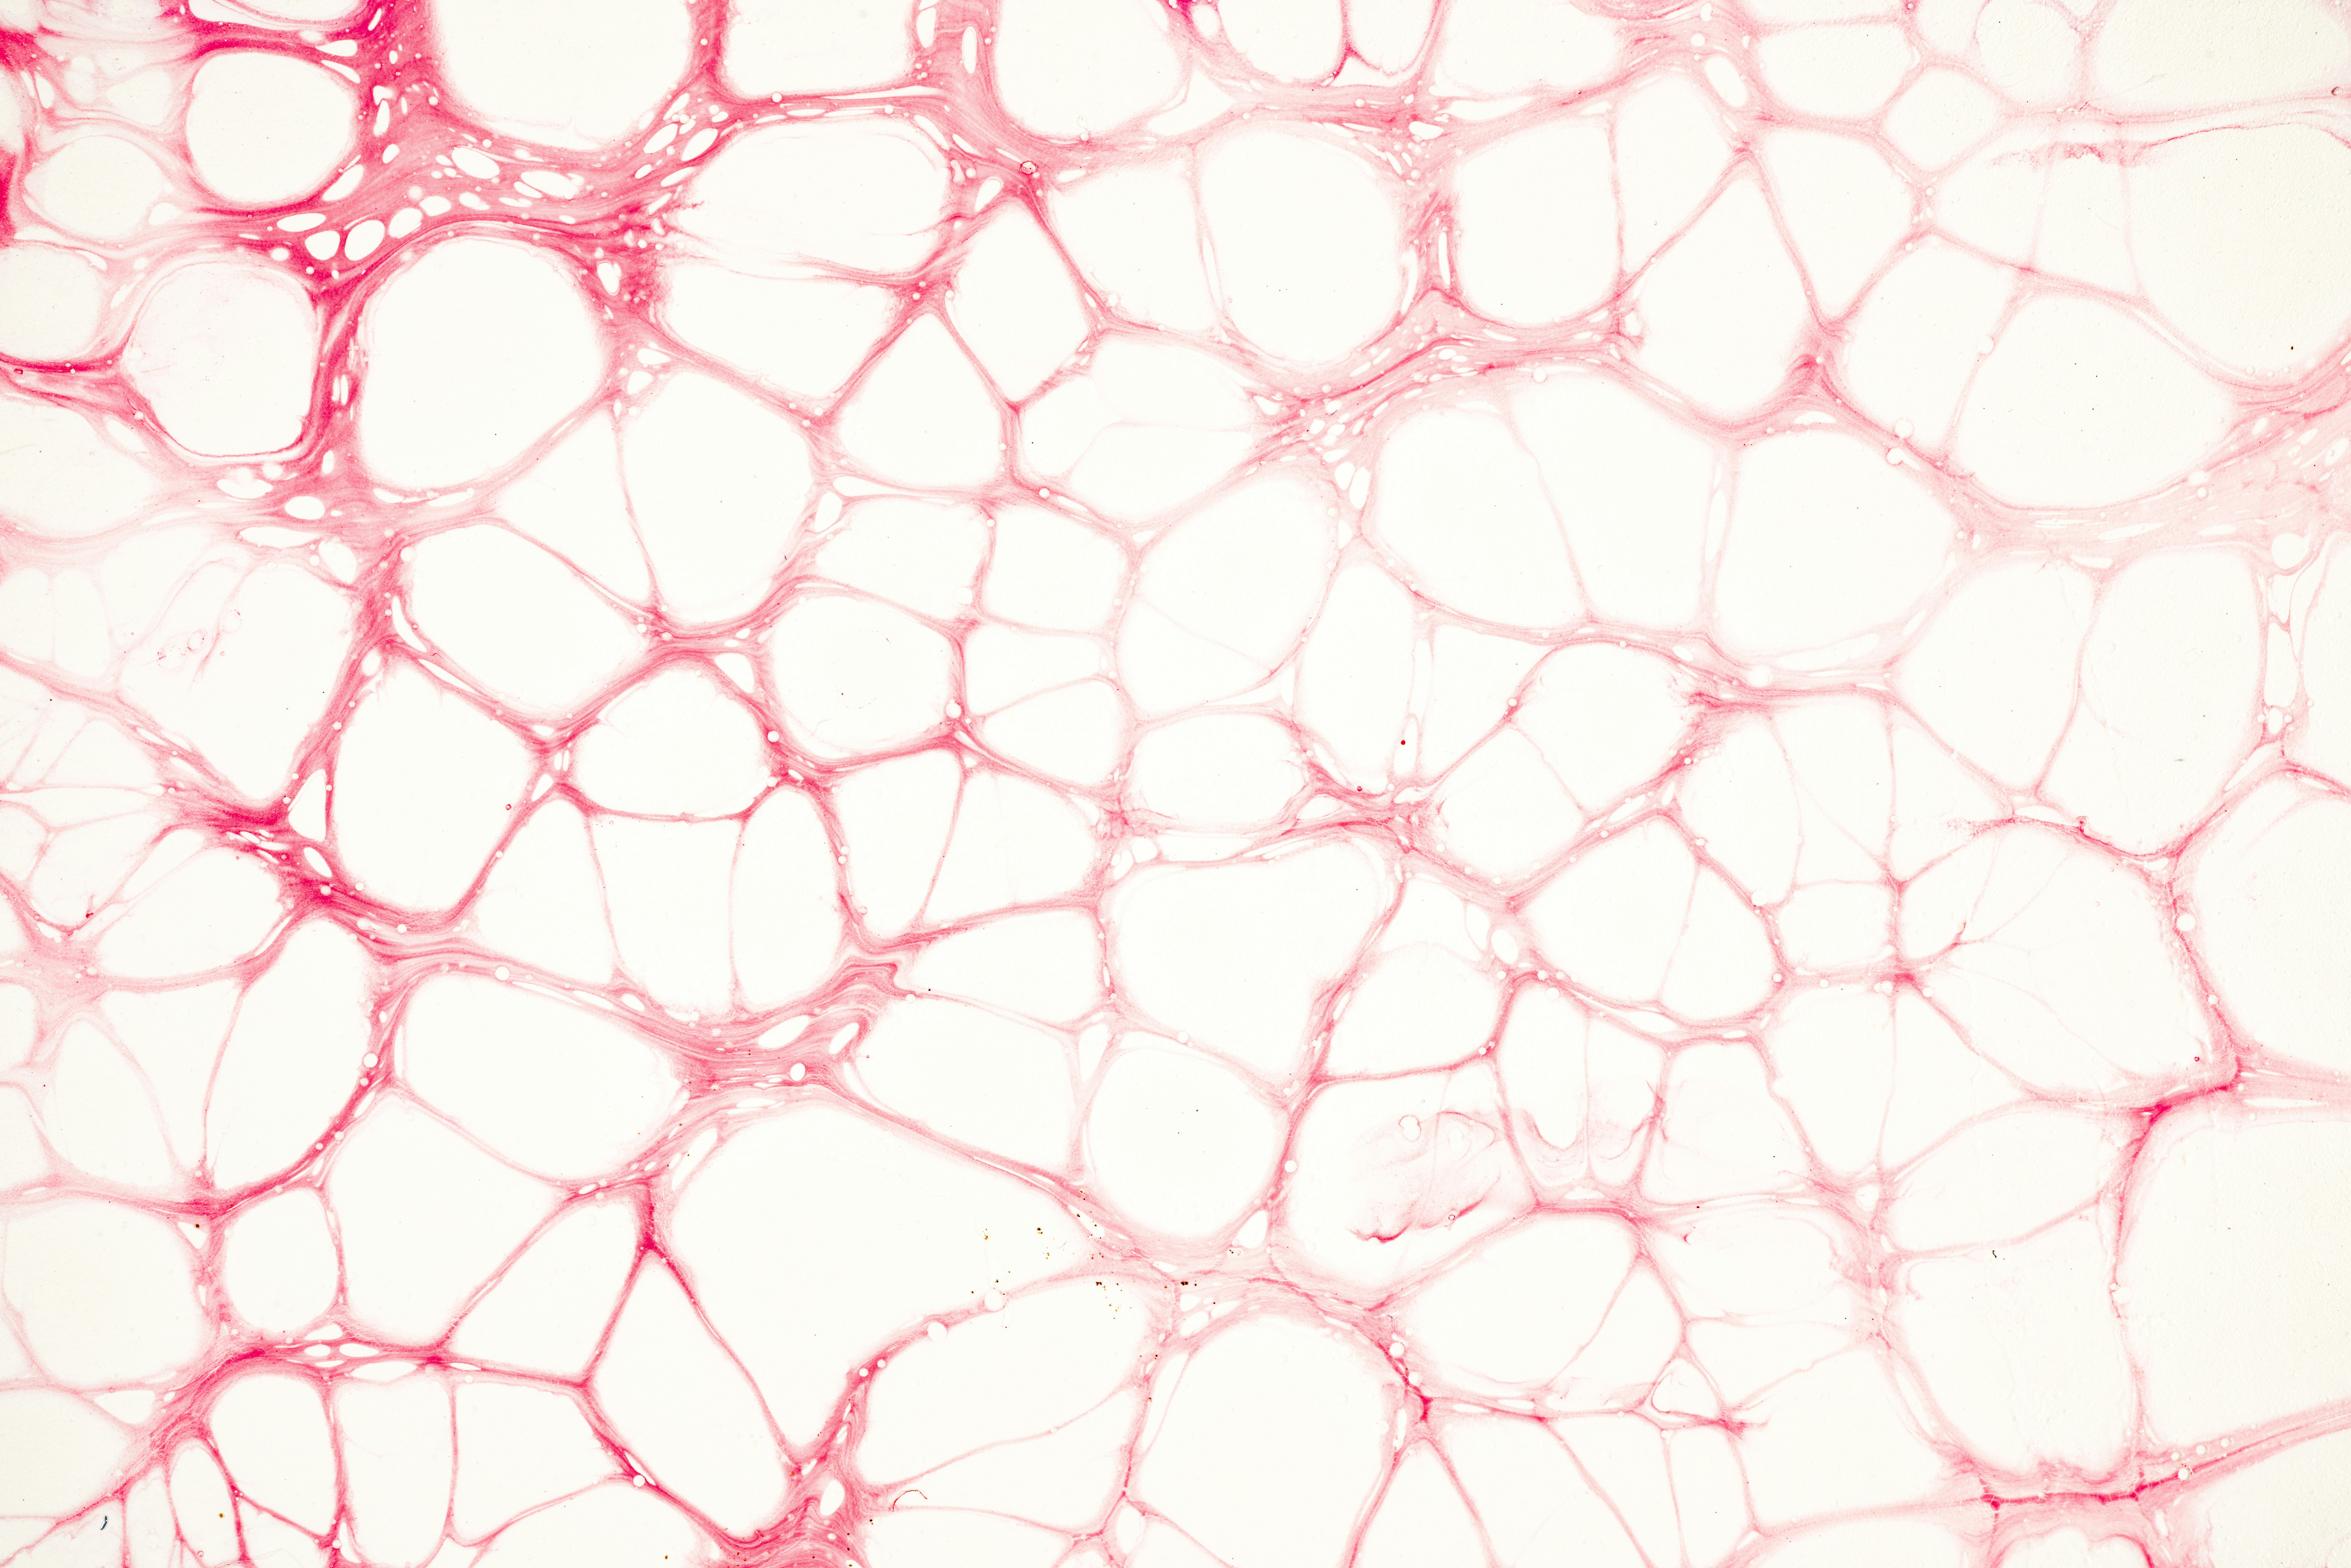

지주막하 출혈(Subarachnoid Hemorrhage, SAH)은 뇌를 둘러싸고 있는 세 층의 막 중 하나인 지주막 아래 공간에 출혈이 발생하는 상태를 말합니다. 이 출혈은 주로 뇌동맥류 파열로 인해 발생하며, 매우 심각하고 급박한 상태입니다. 주요 증상은 다음과 같습니다.